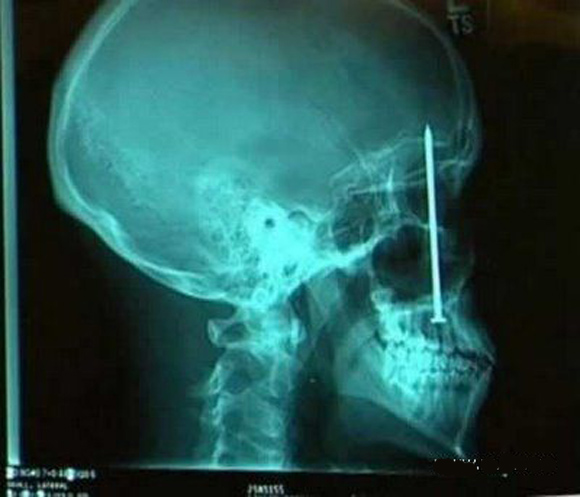

Unusual X-rays

See what can be overheard in the human body.

10-inch nail in his head stayed 6 days: